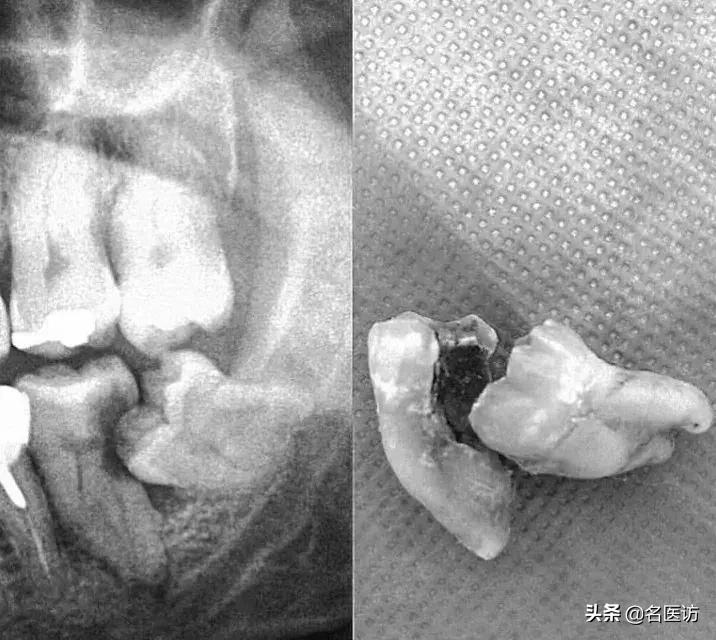

牙齿在颌骨内由于位置不正,不能萌出到正常的咬合位置,这样的牙齿称为阻生牙。最常见的阻生齿是下颌第三磨牙,其次是上颌第三磨牙和上颌尖牙。据统计,成人中患阻生齿者至少占20%。这种阻生齿和覆盖在它上面的牙龈之间,很容易藏污纳垢,滋生细菌,引起口臭及磨牙龋坏,当身体抵抗力下降时,常常会发生炎症。

2.龋齿:阻生的智齿与第二磨牙之间容易积存食物残渣,而且不易清洁,很容易形成智齿和第二磨牙的龋齿而发生疼痛。